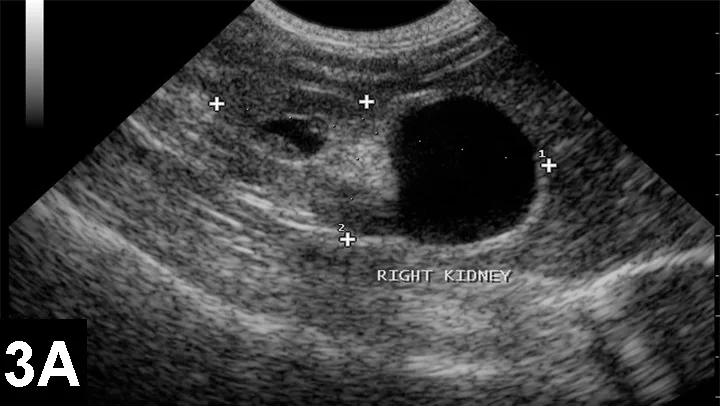

UltrasonographyUltrasonography may be used to diagnose some gastrointestinal disorders, including ileus, intussusception, and enteritis; abdominal effusion from hemorrhage, peritionitis, or ruptured bladder; some congenital renal diseases (Figure 3); and pneumothorax and some heart defects.